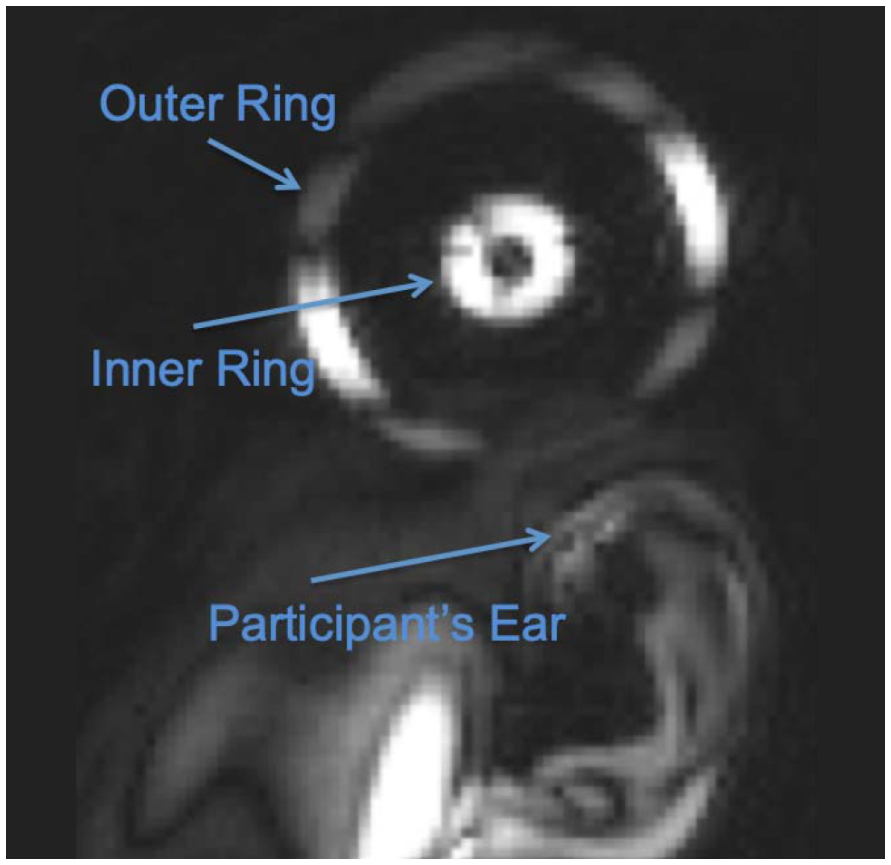

下方左側圖像顯示換能器定位標記的 MRI 影像。